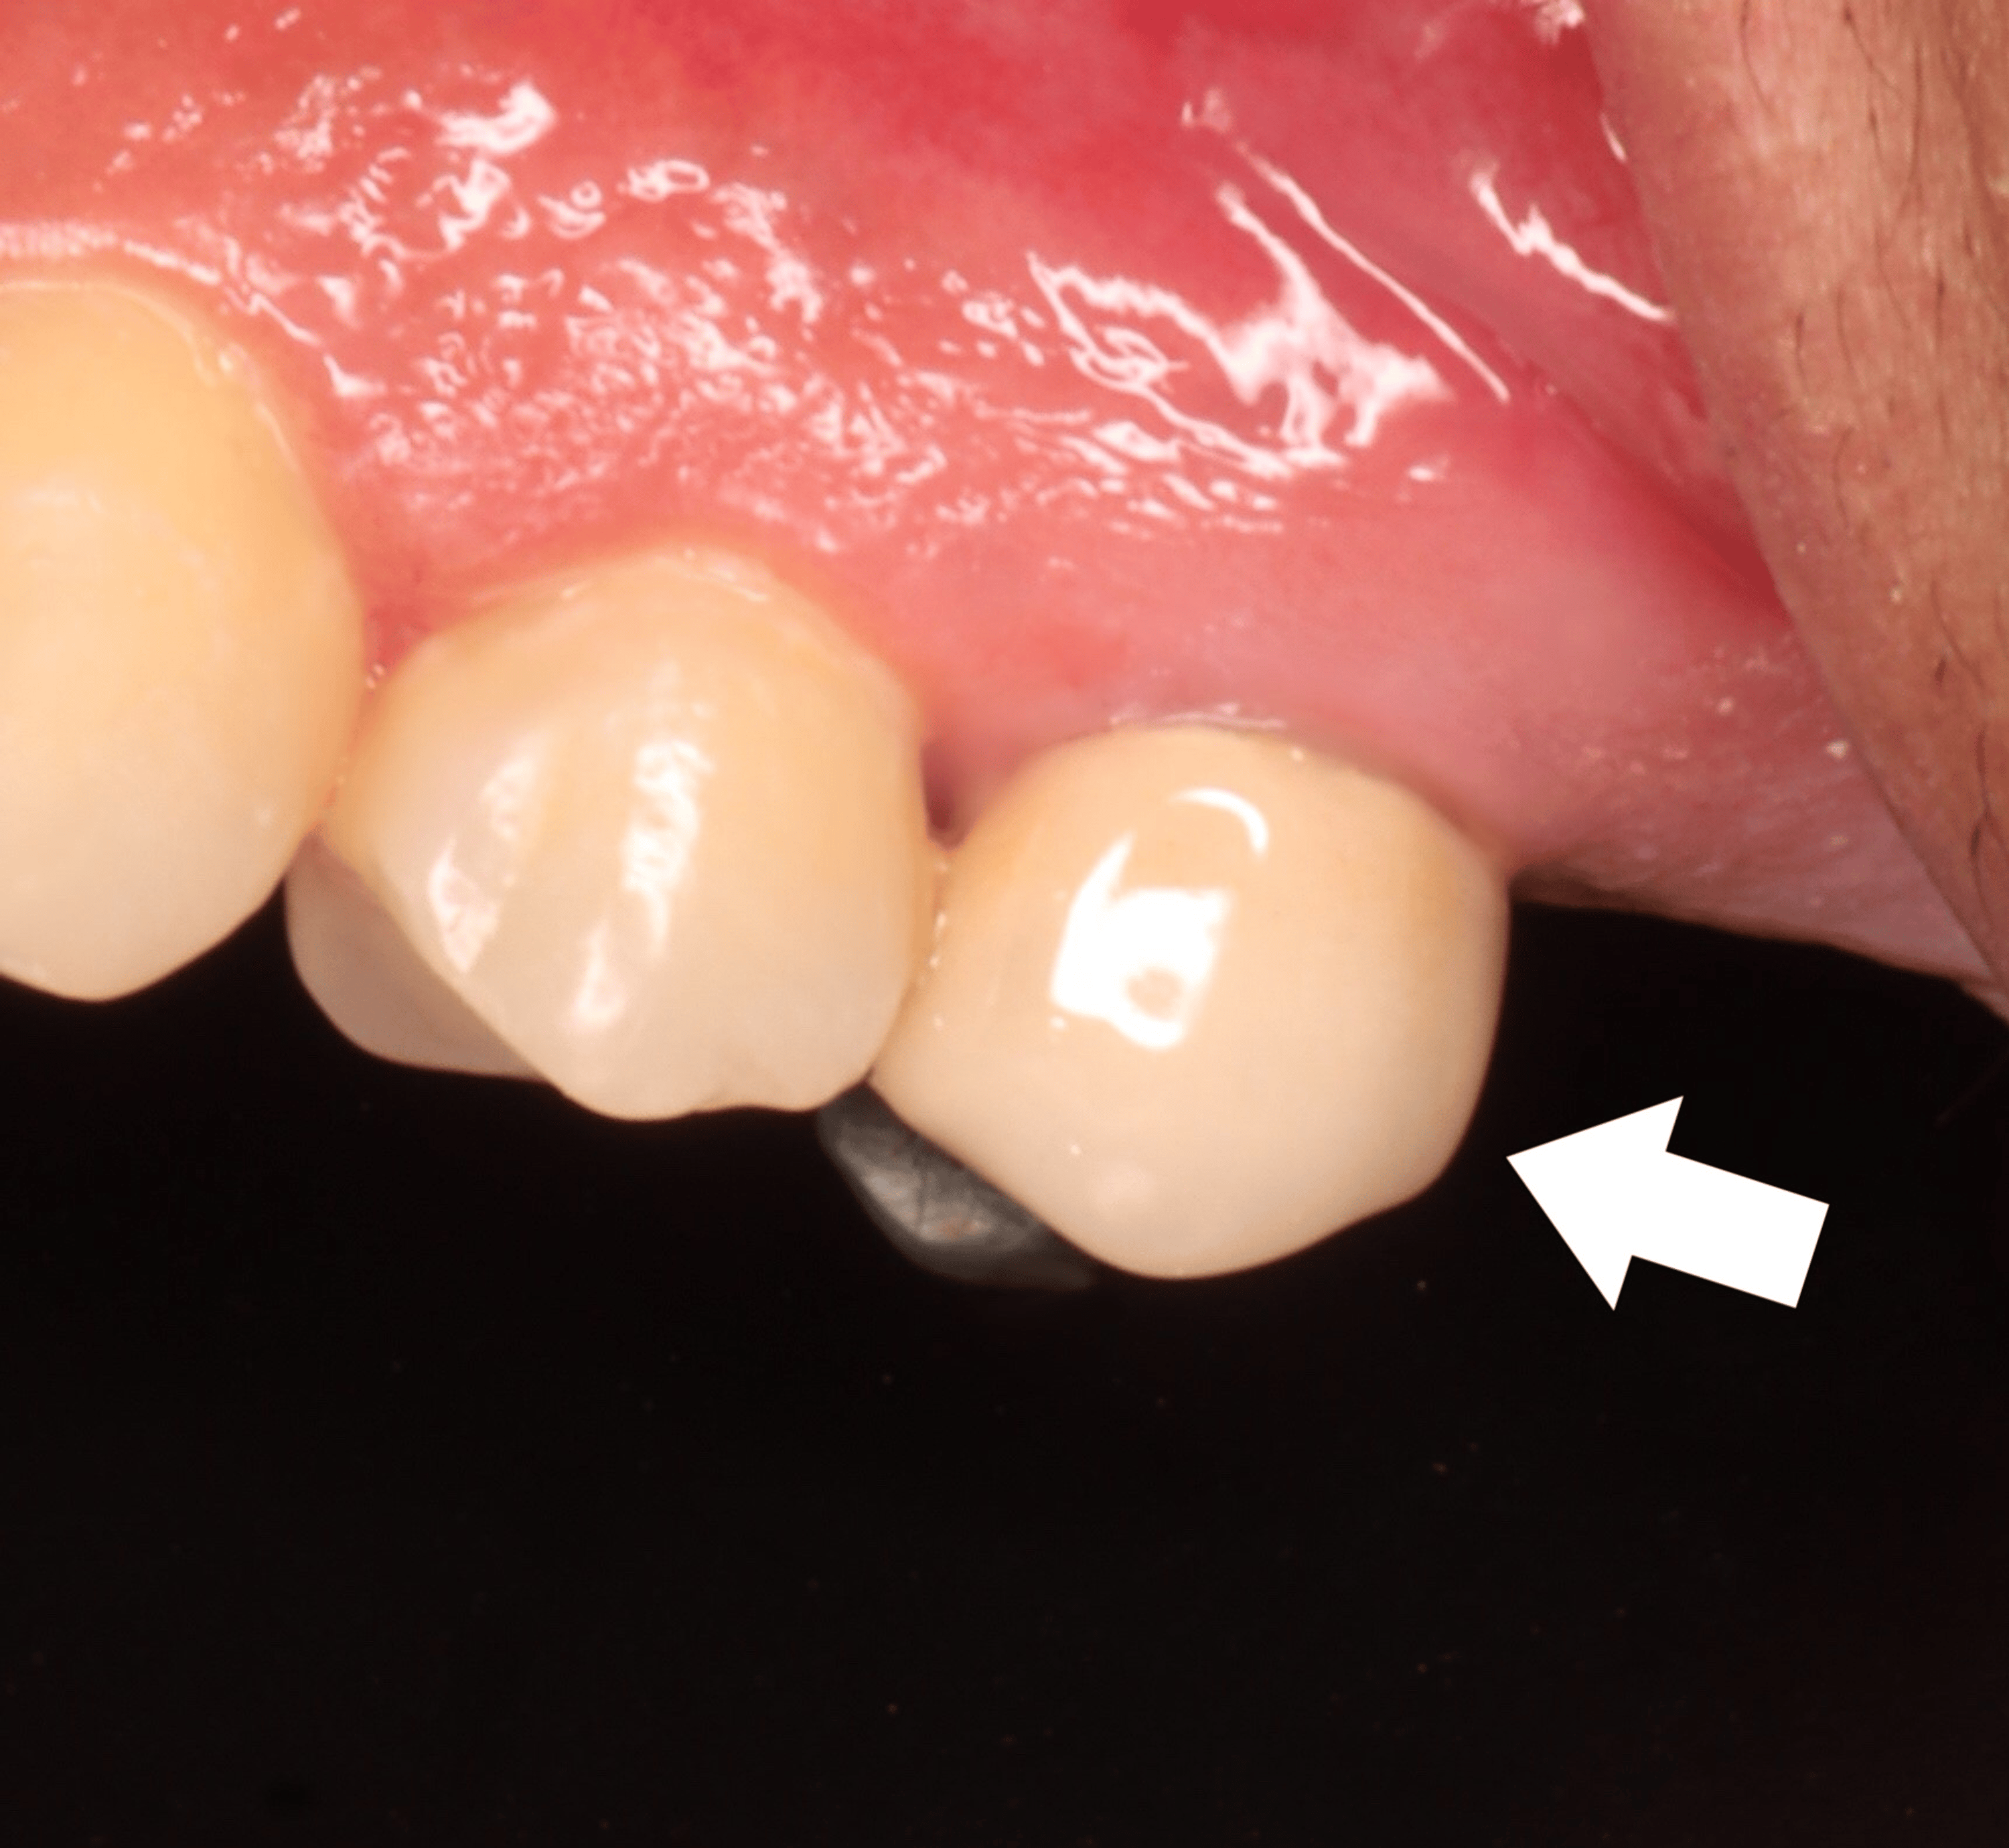

Figure 1 from Interappointment Flareup in Endodontics A Case Report Endodontic Flare Up Ppt 2) they can be caused by. Flareups during root canal treatment can be caused by mechanical, chemical or microbial factors. Causative factors comprise mechanical, chemical and/or. 5 likes • 1,049 views. It defines flare ups as acute exacerbations of periradicular pain or swelling. Flare up is defined as pain or discomfort or swelling that requires an. Endodontic Flare Up Ppt.